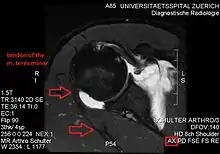

Imaging

Atrophy of the teres minor muscle is often a consequence of a rotator cuff tear, but common isolated teres minor atrophies have also been found. A quadrangular space syndrome causes excessive and or chronically compression of the structures which pass through this anatomical tunnel. The axillary nerve and the posterior humeral circumflex artery pass through the space. People affected note shoulder pain and paresthesia down the arm first and foremost in abduction, extension, external rotation and overhead activity. Selective atrophy of the teres minor muscle has been seen and pulled together directly with compression of the corresponding axillary nerve branch or posterior humeral circumflex artery. Fibrous bands, cysts of the glenoid labrum, lipoma or dilated veins can occupy the quadrilateral space pathologically. Similar symptoms are common with anterior shoulder dislocation, humeral neck fracture, brachial plexus injury and thoracic outlet and inlet syndrome. It is important to include those pathologies for a complete as possible differential diagnosis.

Ultrasonography is a tool to detect a fatty degenerative atrophy of the teres minor and shows in affected muscles increased echogenicity and betimes a slight reduction in muscle bulk. MR imaging helps to consolidate the diagnosis of neurogenic muscle atrophy. Extracellular edema after traumatic events causing neural damage show an increased signal intensity on T2-weighted MRI sequences and normal intensity on T1-weighted sequences. Posterior humeral circumflex artery compression and reduced blood flow in stressful arm positions and or maneuvers can be diagnosed by a Doppler ultrasonography. The nerve should be detected adjacent to the vessel. In an elevated arm position the axillary neurovascular bundle can be seen at the posterior axillary fold just before it perforates the deltoideus, while the posterior course is well visible in the neutral position. For a detailed assessment of the artery, a MR angiography is required. The major task of an ultrasonographic examination is to rule out any space occupying mass. Additional electromyography is helpful to reveal any decelerated nerve conduction velocity, and thus denervation of the concerned muscle.[6]